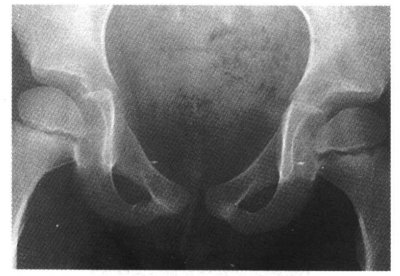

11.坐骨、耻骨软骨联合处不规则愈合,为正常变异,一般为双侧对称,有时仅为一侧,不要误认为骨缺血坏死(图11)。

图11 坐、耻骨联合处不规则愈合,不要误认为坐、耻骨联合处缺血坏死